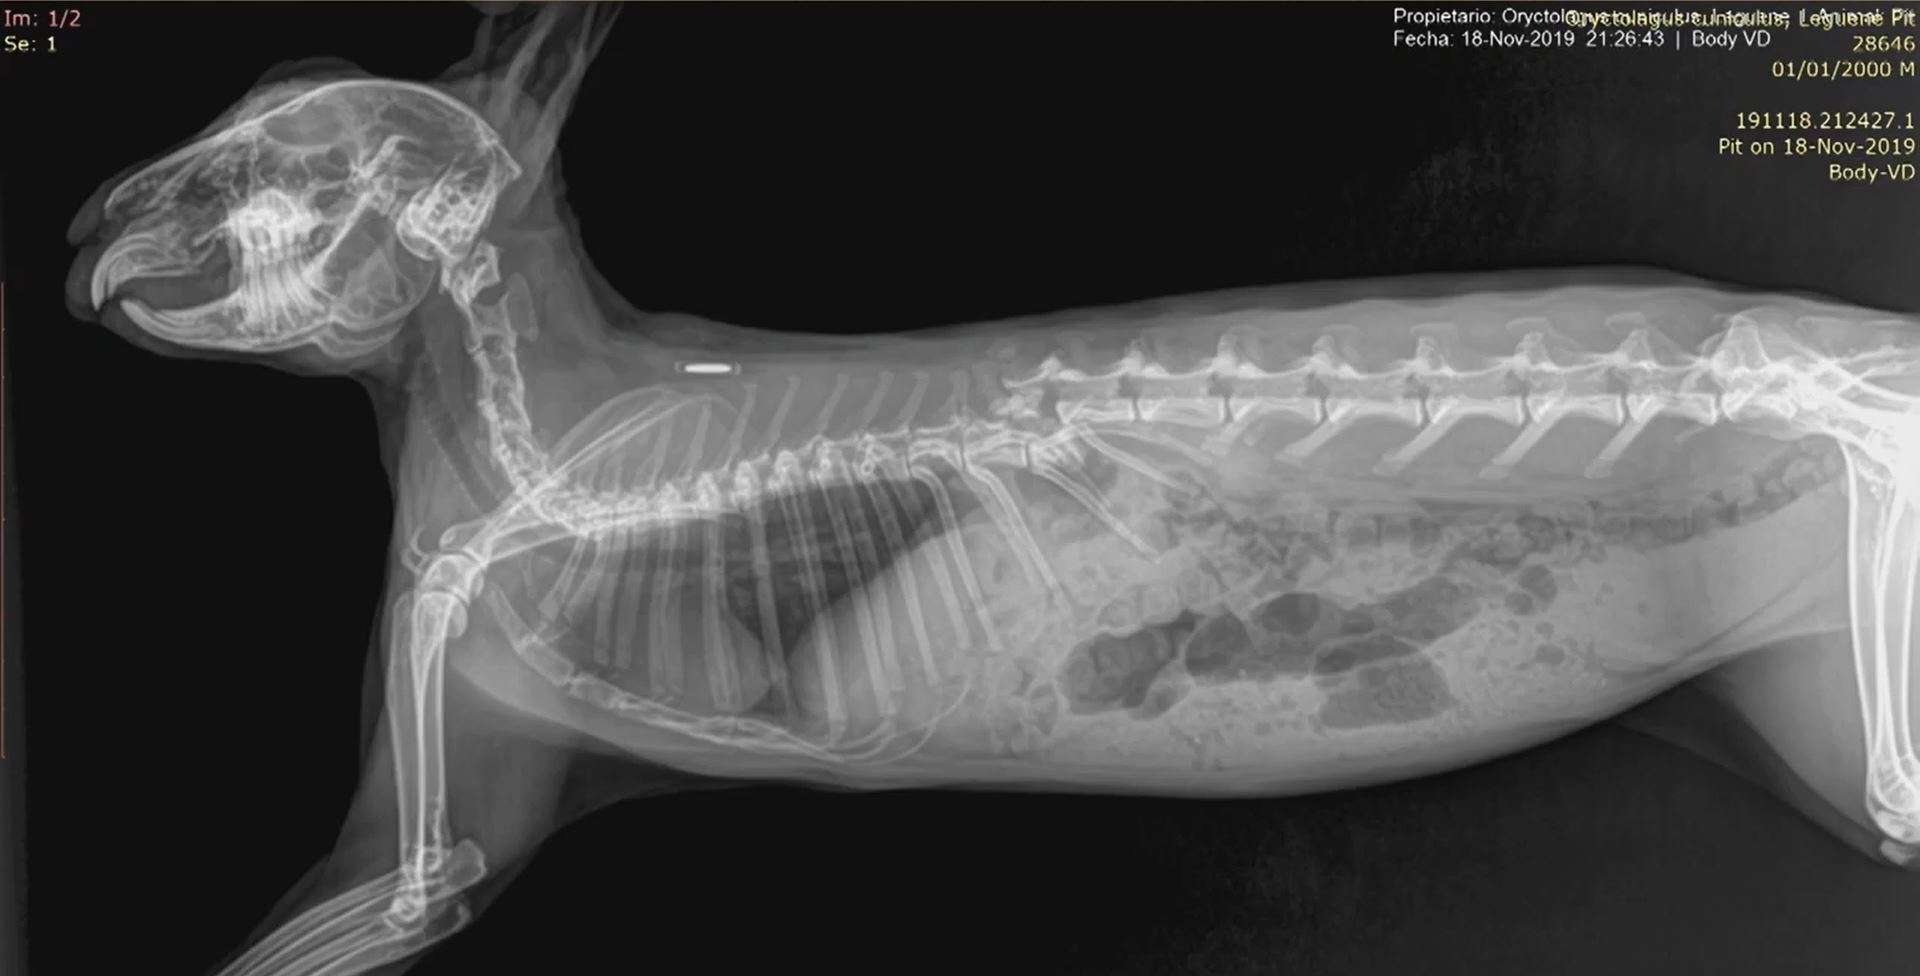

Animales exóticos veterinaria

Animales exóticos en la clínica veterinaria

Andrés Montesinos. Doctor en veterinaria y máster en investigación terapéutica. Especialista acreditado por AVEPA en medicina y cirugía de animales exóticos.